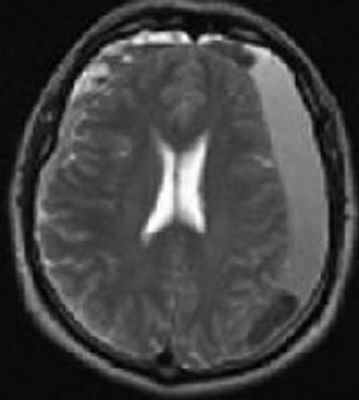

Субдуральная гематома обычно возникает вследствие разрыва вен. Причины субдуральной гематомы – травма, антикоагулянтная терапия, резкая декомпрессия при шунтировании желудочков по поводу гидроцефалии. Очень редко встречаются субдуральные гематомы при разрыве аневризм и АВМ. Клинические проявления связаны смасс-эффектом. Частота субдуральных гематом составляет около 1 случая на 10 тысяч населения. Располагаются субдуральные гематомы по конвекситальной поверхности, изредка, вдоль межполушарной щели и намёта, в области задней черепной ямки. Может быть сочетание субдуральной гематомы с кровоизлиянием в соседние участки мозга. прогноз в этих случаях неблагоприятный. Отображение гематомы на КТ и МРТ зависит от их давности. Субдуральные гематомы имеют форму серпа.

МРТ головного мозга. Аксиальная Т2-взвешенная МРТ. Подострая субдуральная гематома.